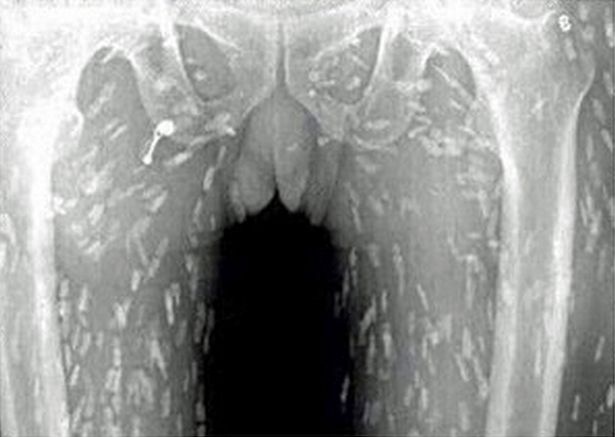

เว็บไซต์ข่าวมีร์เรอร์แชร์ภาพเอ็กซ์เรย์ชวนอึ้งของชายผู้รักการกินซูชิเป็นชีวิตจิตใจ ที่หารู้ไม่ว่าสิ่งที่ชื่นชอบกำลังทำให้ร่างกายของเขาถูกทำลาย หลังภาพเอ็กซ์เรย์ปรากฏว่าข้างในร่างกายเต็มไปด้วยพยาธิตัวตืด!

ชายชาวจีนผู้รักการกินซูชิรายหนึ่งมาพบแพทย์ หลังจากมีอาการปวดท้องและคันไปทั่วผิวหนัง และก็ต้องผงะ เมื่อภาพเอ็กซ์เรย์ที่ออกมาร่างกายของเขาเต็มไปด้วยพยาธิตัวตืด เป็นผลมาจากการกินซาซิมิมากเกินไป หลังจากเขาจับปลาในน้ำจืดมาแล่กินเองแบบดิบๆ

โดยแพทย์เชื่อว่าอาหารญี่ปุ่นประเภทเนื้อดิบและปลาดิบจะมีการปนเปื้อนสิ่งที่ไม่พึงประสงค์ที่ส่งผลให้มีการติดเชื้อปรสิตได้หลากหลายชนิด

พยาธิตัวตืด เกิดขึ้นจากการบริโภคเผลอไปบริโภคตัวอ่อนของพยาธิตัวตืดเข้าไป พบได้ในปลาที่อยู่ในแหล่งน้ำจืดเช่น แซลมอน (ซึ่งปกติเป็นปลาที่อยู่ในน้ำเค็มแต่จะมาวางไข่ในน้ำจืด) และมันสามารถอยู่รอดในร่างกายของมนุษย์ได้นานเป็นปี และวางไข่ทิ้งไว้ตามส่วนต่างๆของร่างกายและแพร่พันธุ์ได้อย่างรวดเร็ว

และอันตรายยิ่งเพิ่มขึ้นหากมันเคลื่อนตัวไปยังอวัยวะที่สำคัญจะดีกว่าถ้าเรากินอาหารที่ปรุงสุกแล้ว